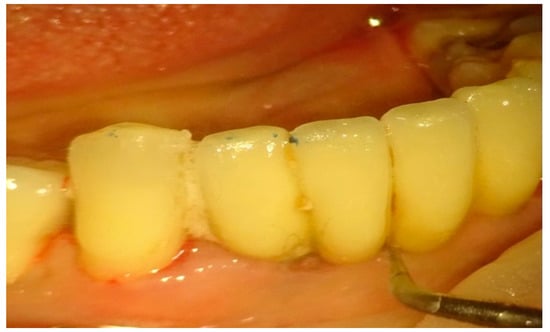

In group B, treated with the OHLLT protocol, a microbiological sampling of the periodontal pockets was made first. Then a supra and subgingival scaling with high-frequency ultrasound was made with a solution of Betadine diluted at 10% (Figure 1). An airflow session with erythritol was performed (Figure 2), and then diode laser treatment with a Sioxyl® solution was performed, irrigating the periodontal pockets with the Sioxyl® solution (Figure 3), leaving the solution for at least 2 min and irradiating with a Wiser diode laser with a peak power of 2.5 W, T-On of 20 microns, T-Off of 80 microns, average power of 0.5 W, duty cycle of 100 microns and frequency of 10 KHz (Figure 4).

Figure 1.

High-frequency ultrasound with betadine diluted to 1/10.